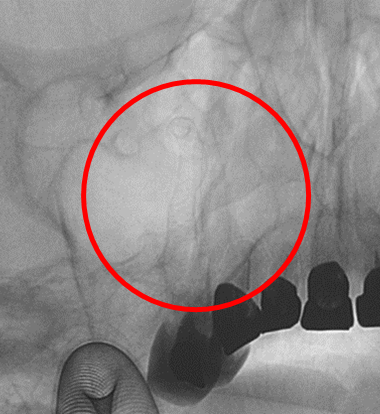

内頚動脈海綿静脈胴部硬膜動静脈瘻

術前の造影写真です。〇内に硬膜動静脈瘻を認め、眼静脈へ動脈血が逆流しています。

硬膜動静脈瘻を塞栓し動脈血の逆流は消失しています。